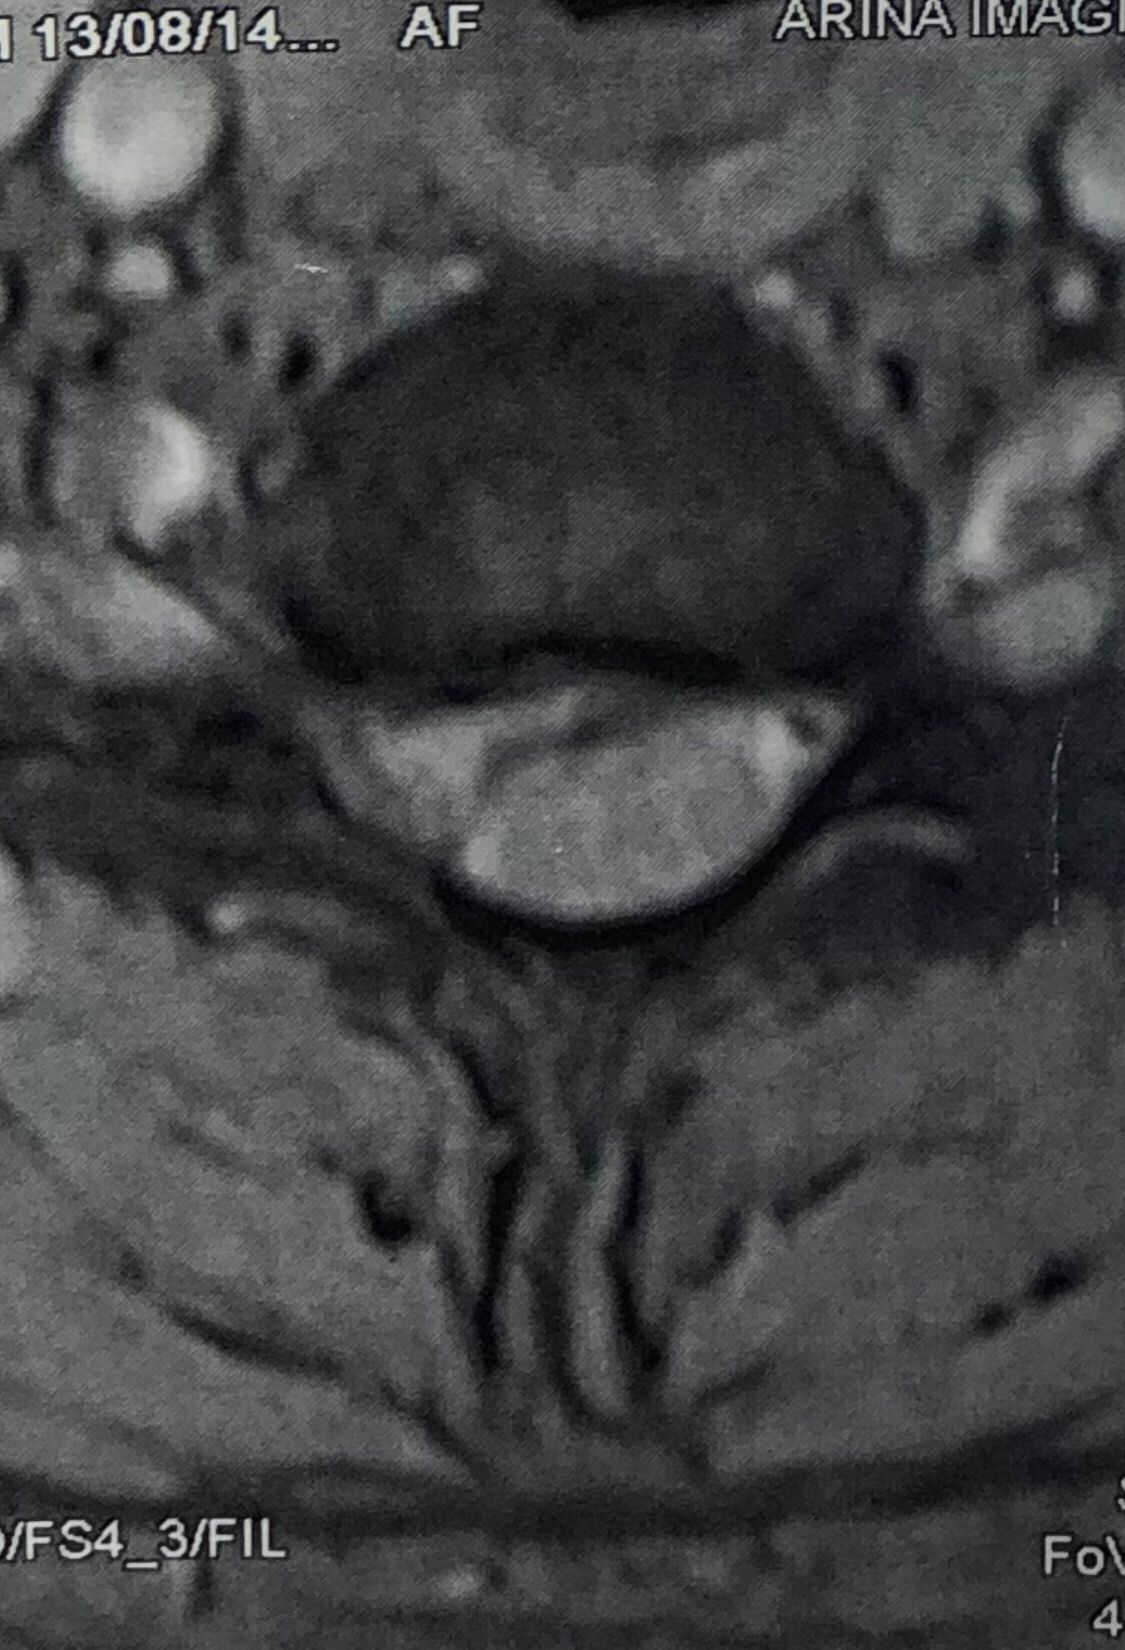

30 year old patient of mine with R. IVF disc extrusion of C 5-6 with R upper extremity pain and numbness without neurological deficit was suggested to have urgent surgery

in his EMG. NCV didn’t have any active axonal loss

got 20 sessions of chiropractic care in one month by me mainly using decompression and C0-C1 prone drop manipulation and 3 sessions of mild adjustment to segments above disc herniation. No direct adjustment to the involved disc extrusion

After treatment:

reduction of R. IVFdisc extrusion by more than 50%.

90% improvement in patient’s signs and symptoms and preventing of unnecessary expensive surgery

following one month of cervical chiropractic spinal treatments